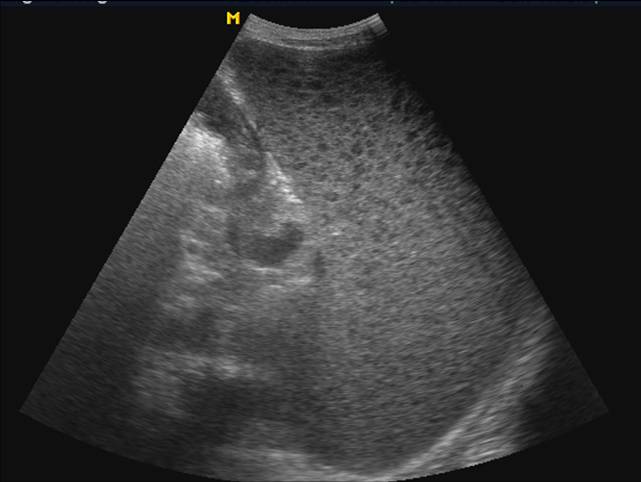

声像表现

1、脾大

2、急性期脾梗死

单发或多发,大小不一

单发者楔形,基底宽,凸面向包膜,尖端指向脾门

内部回声呈大片回声减低区

中央发生坏死液化出现无回声区

CDFI梗塞区缺乏血流灌注因而不显示彩色血流信号。